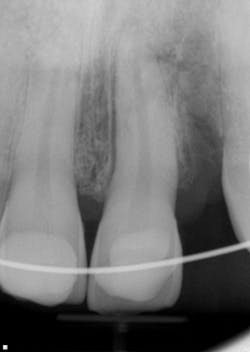

Twelve days later, the patient returned with the following assessment and treatment (figure 4):

- Overall, the patient was feeling better, with reduced swelling in all soft-tissue areas.

- Chief concern: His bite was off. This was adjusted.

- Cold testing: No response with No. 9 and slight delay with No. 8.

- Tooth appeared more stable within the alveolus; the splint was removed between Nos. 8 and 9, but not from canine to canine.

- It was recommended that we commence with endodontic treatment on No. 9 and maintain a watch on No. 8 for any irreversible changes.

- Tooth No. 9 was opened up; the pulp was necrotic. The chamber was cleaned out, irrigated, and calcium hydroxide medicament was placed. It was recommended that we change out the dressing two to three more times over the course of the next few months, so stabilization of the tooth could continue and a better prognosis could be determined.

Figure 4